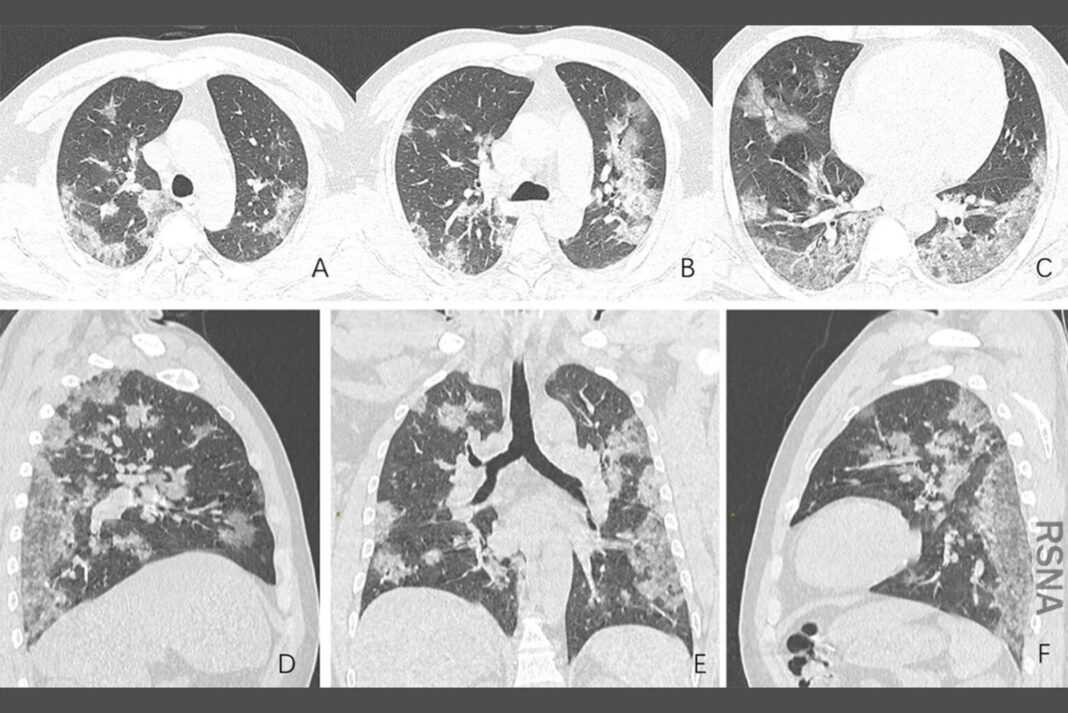

Καθώς η omicron τροφοδοτεί το κύμα νέων περιπτώσεων, οι Αμερικανοί αντιμετωπίζουν ξανά την εικονική μάθηση Σε μια έκθεση της Τετάρτης, μια διεθνής ομάδα είπε ότι τα χάμστερ και τα ποντίκια που είχαν μολυνθεί με όμικρον είχαν λιγότερη βλάβη στους πνεύμονες, δεν έχασαν τόσο πολύ βάρος και είχαν λιγότερες πιθανότητες να πεθάνουν.

Ενώ τα ζώα που έχουν μολυνθεί με όμικρον παρουσιάζουν γενικά ηπιότερα συμπτώματα, η ομάδα διαπίστωσε ότι τα επίπεδα όμικρον στους πνεύμονες των τρωκτικών ήταν το ένα δέκατο ή λιγότερο από τα επίπεδα άλλων παραλλαγών.